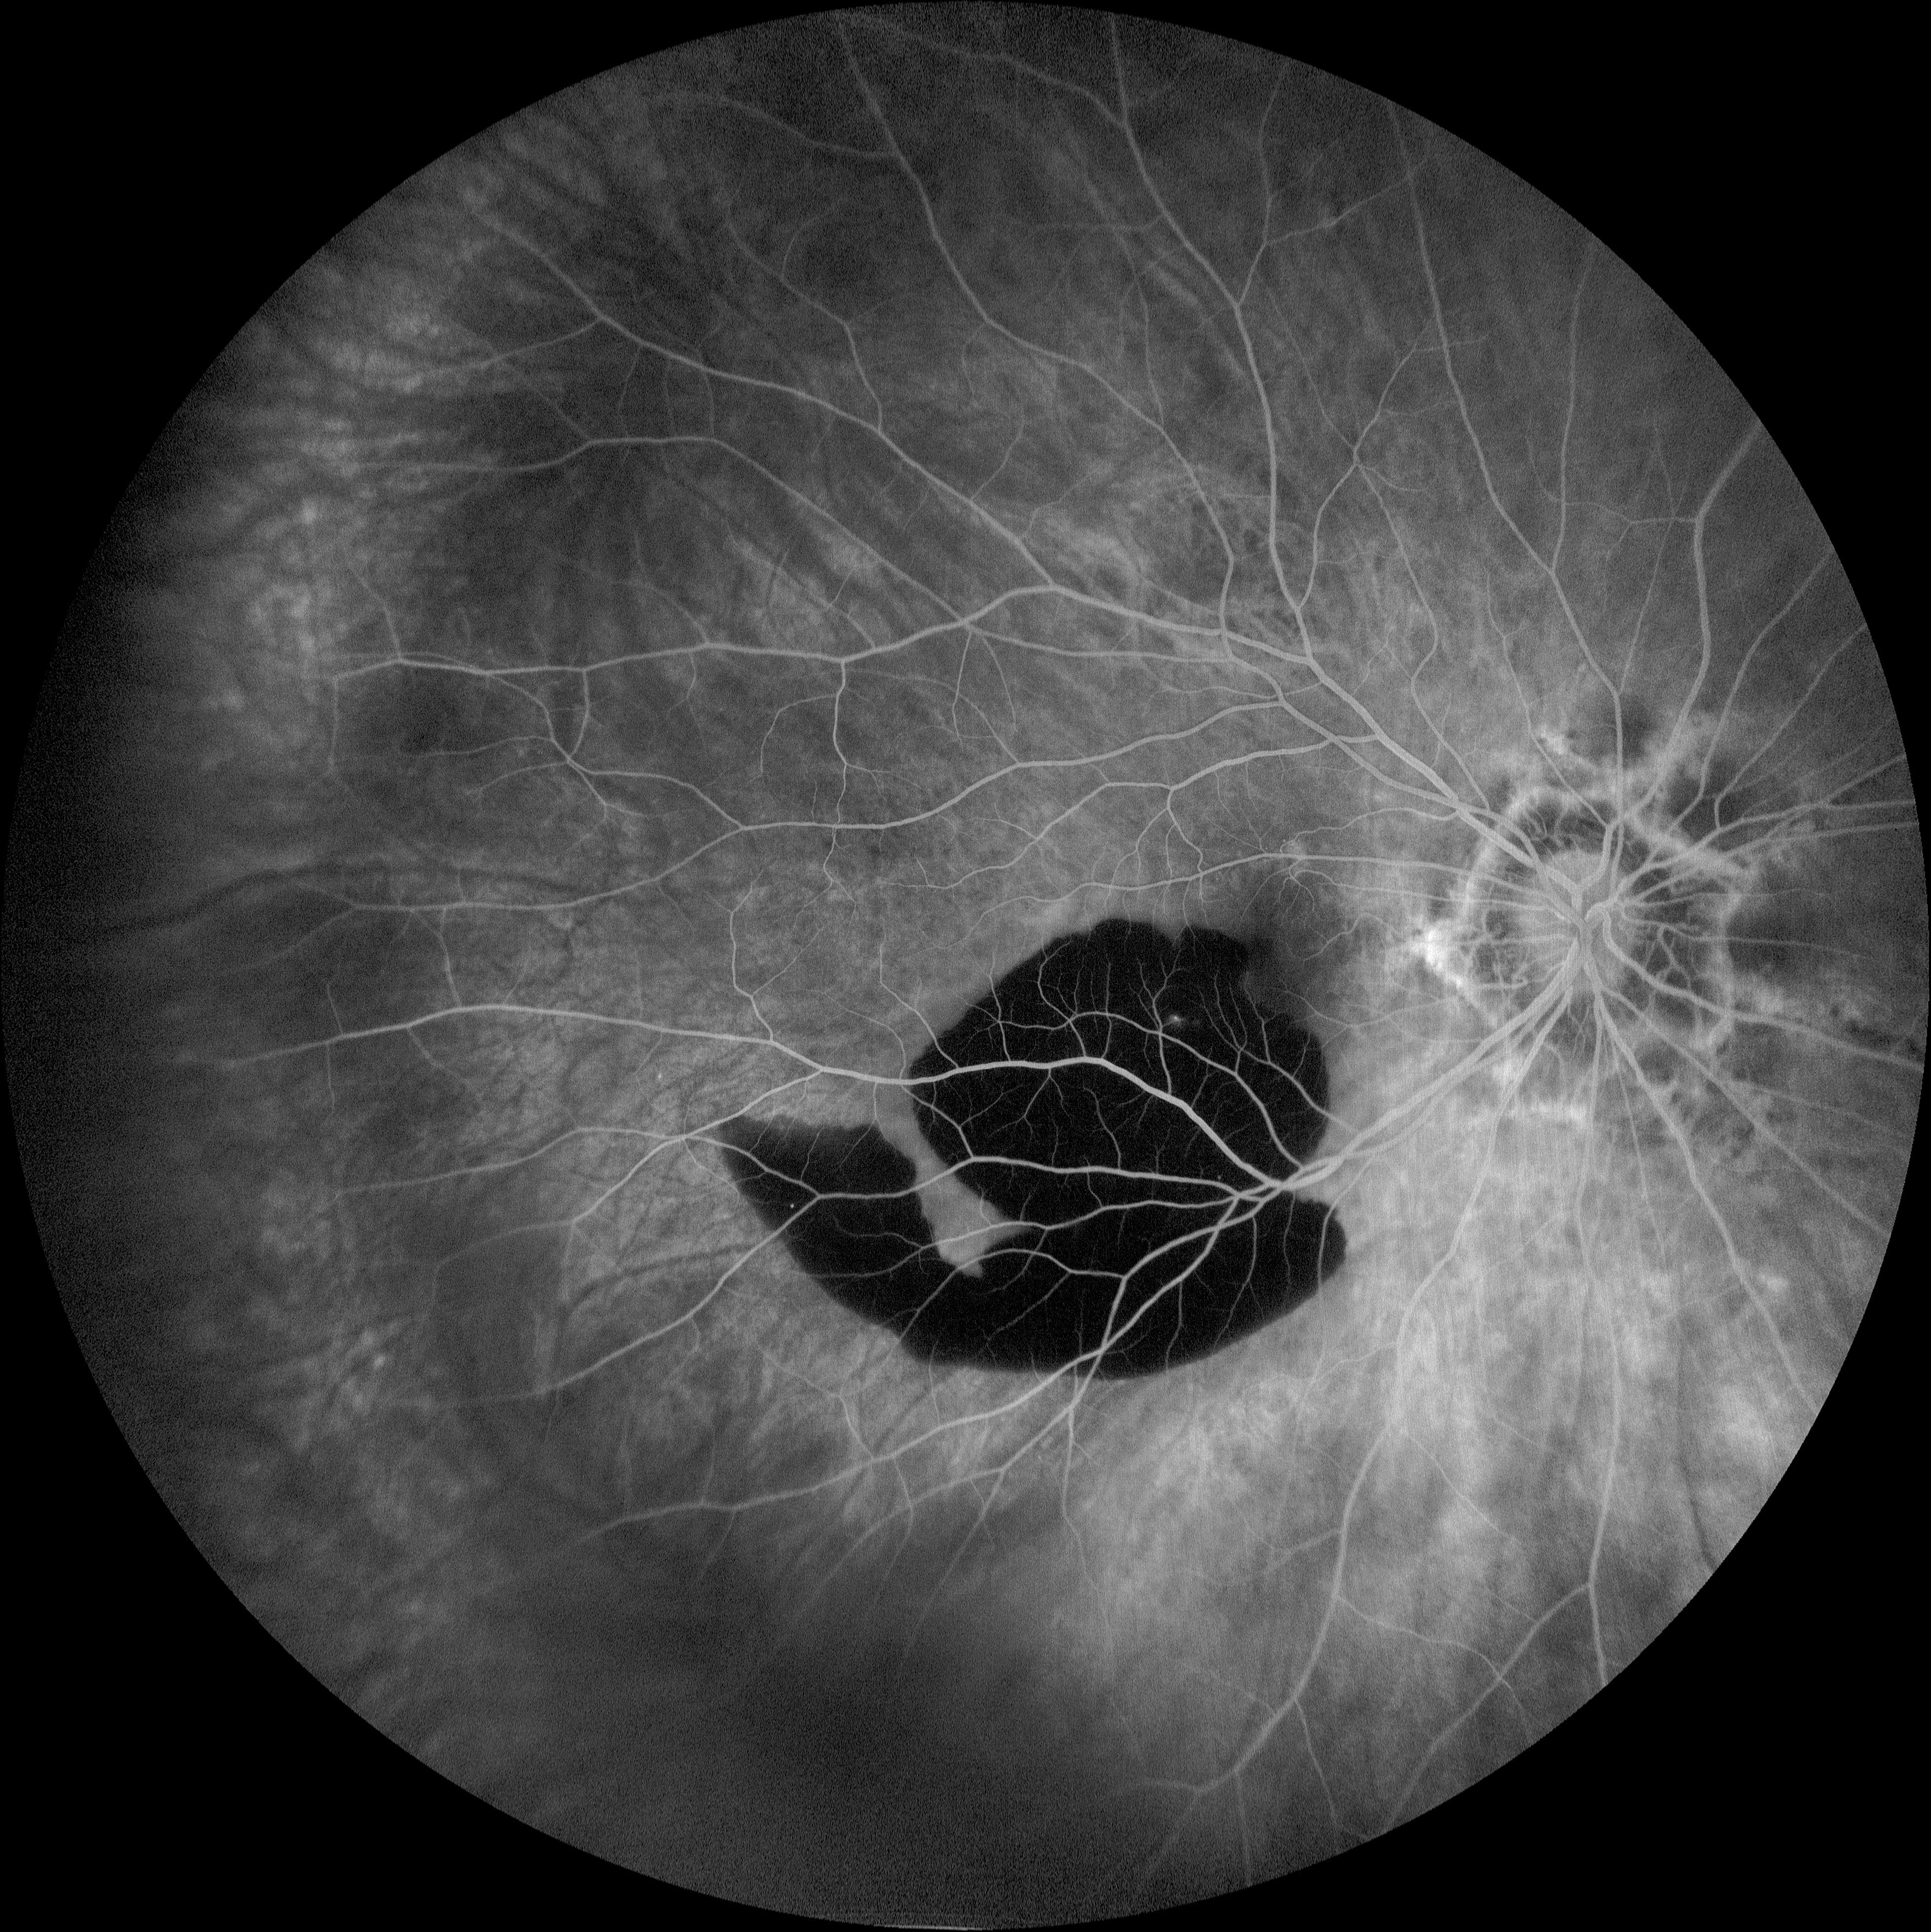

Lesion Presented by Ashley Schell, OCT-C This photograph received Honorable Mention, Fluorescein Angiography (45° - 60°) in the 2025 OPS Scientific Exhibit. Filed Under Cornea OPS Photo